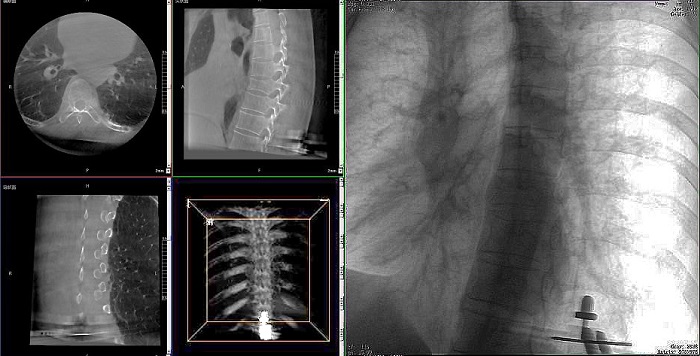

患者:71歲,男性,胸8椎體壓縮性骨折

術(shù)式:機(jī)器人輔助經(jīng)皮釘棒系統(tǒng)復(fù)位內(nèi)固定手術(shù)

①機(jī)器人輔助胸椎手術(shù)操作難點(diǎn)之圖像采集

胸椎緊鄰肺部,患者的呼吸運(yùn)動(dòng)會(huì)造成椎節(jié)的相對(duì)移動(dòng),獲取清晰、穩(wěn)定的影像較為困難。高質(zhì)量的影像是精準(zhǔn)導(dǎo)航的重要前提,胸椎手術(shù)中,如果呼吸造成的移動(dòng)無(wú)法得到有效控制,則會(huì)降低導(dǎo)航的精度,增加手術(shù)風(fēng)險(xiǎn)。人體深吸氣胸圍與深呼氣胸圍的差值約為6~8厘米。

高清三維成像:普愛醫(yī)療精研三維成像技術(shù)13年,自研的三維C形臂可為手術(shù)提供清晰、穩(wěn)定的三維圖像,為醫(yī)生精準(zhǔn)開展胸椎手術(shù)提供影像保障。

快速掃描:麻醉師通過(guò)適當(dāng)?shù)暮粑刂疲浜先SC形臂的快速掃描模式,可以在短時(shí)間內(nèi)完成圖像采集,減少因呼吸運(yùn)動(dòng)造成的圖像干擾。